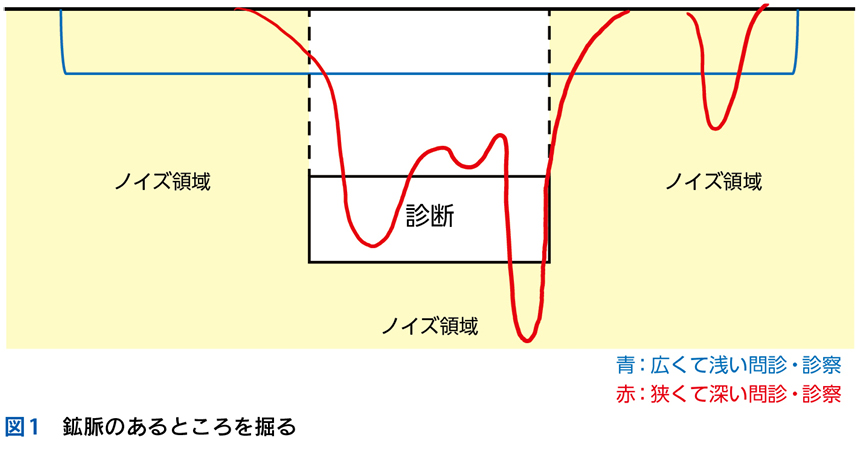

▶ 分析的診断推論とは,論理的に選び出した,可能性のある複数の診断を検討することである。膨大な数の疾患の中から可能性のある診断群を選び出すためには,まず疾患全体を含む空間の中に,「この内側に確実に真の診断がある(この外側には確実に真の診断はない)」という「枠」を置くことが必要である。仮にそうせずに推論を進めるのであれば,広大な空間内から行き当たりばったりで疾患を選んでいくことになる。これは要するに直観的診断の繰り返しであり,システム1が磨かれていなければ当たるも八卦,当たらぬも八卦で診断にたどり着けるかどうかわからない。

▶ 疾患全体という空間内に診断の可能性を限定する「枠」(フレーム)を置くことは,分析的診断の必要条件となる重要な一歩である(図2)。これを筆者は「フレーミング」と呼ぶ。

3 プロブレム/問題のyield

▶ フレームの広さを決めるのは,定義された問題の“yield”である。yieldとは「産み出す」というような意味で,定義された問題がどれほど診断に資するかによって,問題のyieldが高い(high yield),低い(low yield)という使い方をする。high yieldな問題によるフレームは狭く,可能な診断の数を大きく絞り,診断をぐっと近づける。言い換えれば,ある診断(の一群)に対して特異度が高い。一方で,low yieldな問題によるフレームは広く,鑑別診断を意味のある数に絞ることに役立たない(図3)。

5 ノイズと多元論

▶ 「ノイズ」は,筆者的には臨床推論においてきわめて重要な概念であるため,第4章で詳述するが,フレーミングに関わるのでここで簡単に紹介しよう。ここでは「ノイズ」を,「患者の持つ情報のうち診断と直接的には関連しないもの」を指す語として使用する。対義語(診断と関連する情報)は「シグナル」である。星座のたとえで言えば「シグナル」は星座を構成する星,「ノイズ」は星座を構成しないが近傍にある「くず星」を指す(図4)。